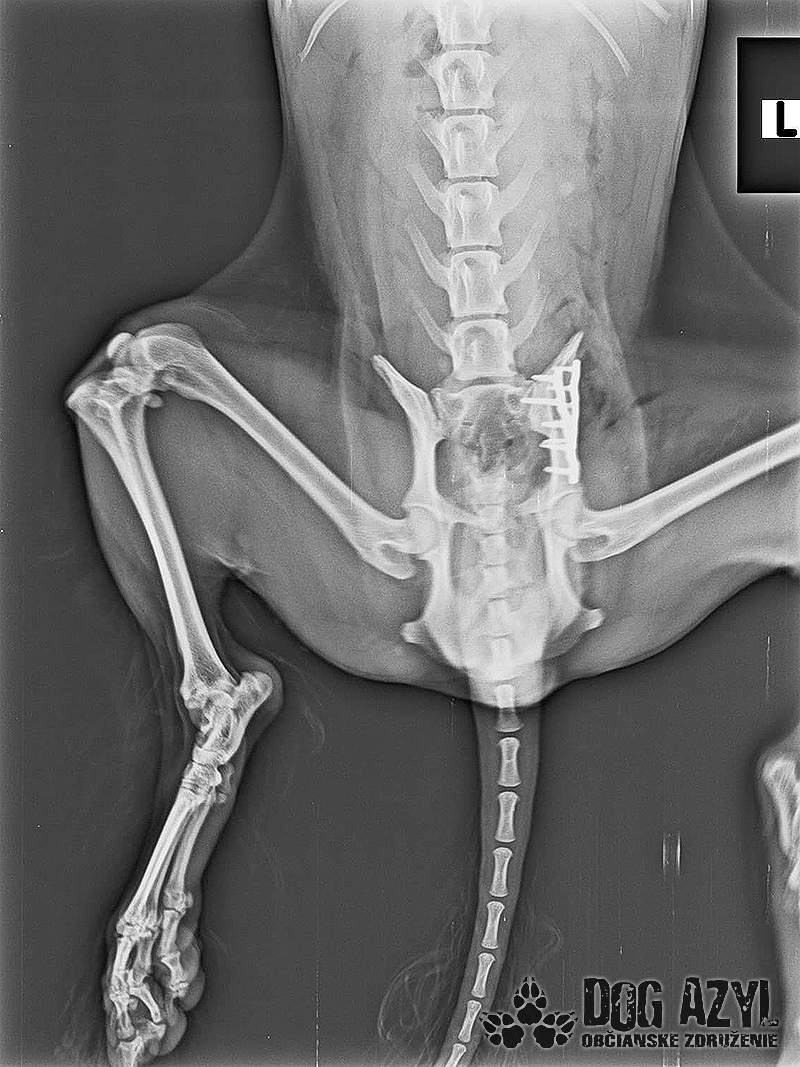

Mia, narodená máj 2015, sa našla zrazená v obci Bodza. Mala obrovské šťastie, že ju nálezkyňa ihneď naložila do auta a utekala s ňou k nášmu veterinárovi. Bola v katastrofálnom stave a mala obrovské bolesti :( Keďže Mia bola čipovaná, hneď sme sa dopátrali aj k majiteľom, ale na druhej strane telefónu nám bolo oznámené, že Miu darovali niekomu ale nemajú kontakt. Tak sme trocha pátrali a vypátrali sme, že Mia bola darovaná "do dobrých rúk" z postele priamo na dvor! Rodina sa tvárila veľmi zodpovedne a láskyplno, ale zrejme nepochopili,že Mia je kastrovaná a už nebude produkovať šteniatka. Po pár neúspešných pokus spáriť ju so samcom putovala do ďalších dobrých rúk" a to k miestnemu alkoholikovi, kde skončila v šope na reťazi a spala na kope hnoja :( Podarilo sa jej nejakým zázrakom ujsť, ale žiaľ skončila pod kolesami auta. Čomu sa vlastne ani nečudujeme, keďže cez tie zlepené chlpy nemala najmenšiu šancu vidieť pred seba. Mia podstúpila veľmi náročnú operáciu panvy, ktorá sa úspešne podarila, ale pri chladnejšom počasí zvykne trocha krívať. Mala tiež zlomený pst na zadnej nohe, ktorý sa zle zrástol a tak jej nechtík rastie trocha krivo a treba ho pravidelne strihať. Vôbec nič jej to však neuberá na kráse a chuti do života :) Mia si hľadá rodinu, ktorá jej vie sľúbiť, že ju nikdy viac neopustí. Je to skôr pokojná fenka, nie je vôbec náročná na pohyb ale na maznanie o to viac :) Veľmi rada sa túli k človeku, je veľmi priateľská a kontaktná. Vôbec jej nevadí spoločnosť iných psíkov ani mačiek ale nepotrebuje ich ku svojej spokojnosti :) Mia je dokonale vhodná do bytu, ale k malým deťom určite nie, má totiž rada svoje súkromie. Ak by sa mala adoptovať k rodinnému domu tak podmienkou je bývanie v dome.